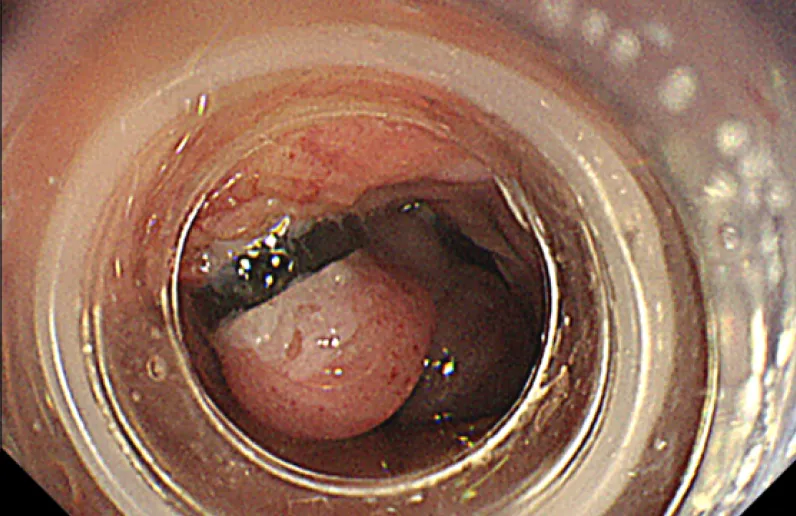

診断時にすでに肝硬変まで進行してしまった患者さまも少なくなく、肝硬変が進行した患者さまでは、肝がん、難治性腹水、肝性脳症、食道・胃静脈瘤(写真1)などさまざまな合併症が生じてきます。当科ではこれらの肝硬変に伴う合併症に対して、それぞれ適切な薬剤や処置を行って治療を進めていきます。

(写真1)食道静脈瘤

食道静脈瘤に対する内視鏡的静脈瘤結歯術